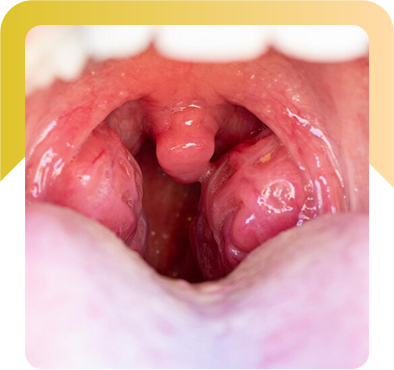

Tonsillitis

- Description: Inflammation of the tonsils, usually due to infection.

- Symptoms: Sore throat, swollen tonsils, difficulty swallowing.

- Treatment: Antibiotics for bacterial infections, or tonsillectomy (surgical removal of the tonsils) for chronic cases.